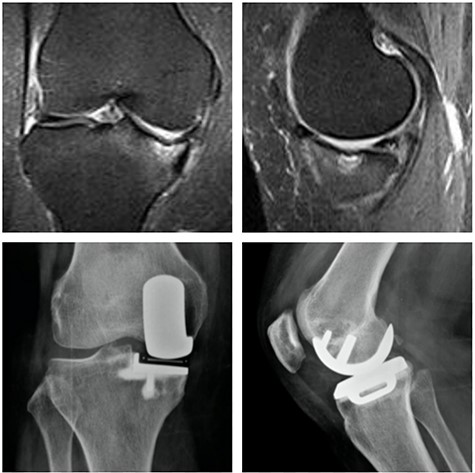

Left knee T2 coronal MRI (top left) showing MP and femoral condyle SIFK with articular failure of both surfaces; Top right: same image (T1); Bottom left: orthostatic anterior view X-ray image of the same patient showing medial compartment bone-on-bone contact; Bottom right: lateral view X-ray image of the same patient.